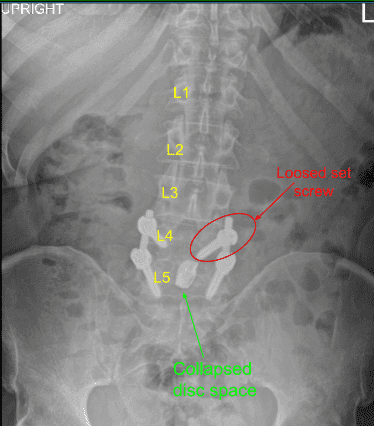

They started having claudication symptoms. They were seen by us and new imaging had been done which showed collapse of the L4-L5 interdisc space along with loosening of setscrew of the left L4.

The set screw from left L4 was found to be dislodged into the soft tissue. It was removed. Further dissection was done on the transverse process of the L4 on the right side There was soft callus present. The decortication of L4 and L5 transverse processes and the pars was performed with intent to achieve fusion in the region.

A small BMP was opened in preparation for the fusion. Revision decompression of the L4-5 was performed with inferior laminectomy of the L3. The bone was used for local autograft. A thorough decompression of the L4 and L5 of the left and right was performed with the use of curettes followed by Kerrison punch. Full decompression could be achieved. A new set screw was put on to the left L4 and torqued in the usual fashion.